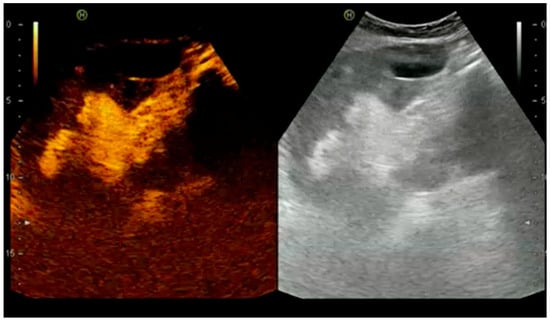

4.1.2. Venous Thrombosis